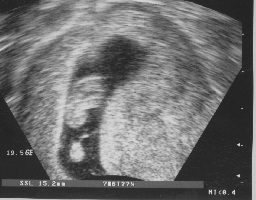

ich nehme zur Downregulierung das Nasenspray Synarela, seit Donnerstag spritze ich Puregon und zum Auslösen soll ich dann Predalon nehmen. Ich muß am Montag zum ersten US, mal sehen, ob sich was getan hat. Bin schon gespannt, wie mein Körper reagiert hat. Läßt Du Dir diesmal 2 zurückgeben?